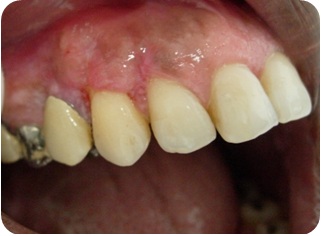

- Figura 1B (Português (Brasil))

- Figura 1C (Português (Brasil))